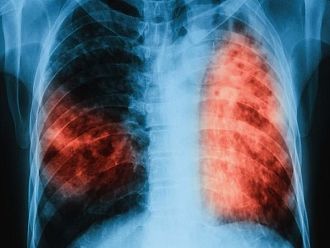

На 24 март отбелязваме Световния ден за борба с туберкулозата – заболяване, което продължава да бъде заплаха за общественото здраве, въпреки напредъка в медицината, припомнят от Министерството на здравеопазването.

Туберкулозата е инфекциозно заболяване, което се предава по въздушно-капков път и може да засегне всеки. Разпространението ѝ е пряко свързано с имунизационния обхват, ранното откриване и навременното започване на лечение.

Въпреки че често се възприема като заболяване от миналото, туберкулозата съществува и днес. Важно е да знаем, че тя е предотвратима и лечима, когато бъде установена навреме.

Ранната диагноза и последователното лечение са от решаващо значение – както за здравето на пациента, така и за ограничаване на разпространението на инфекцията.